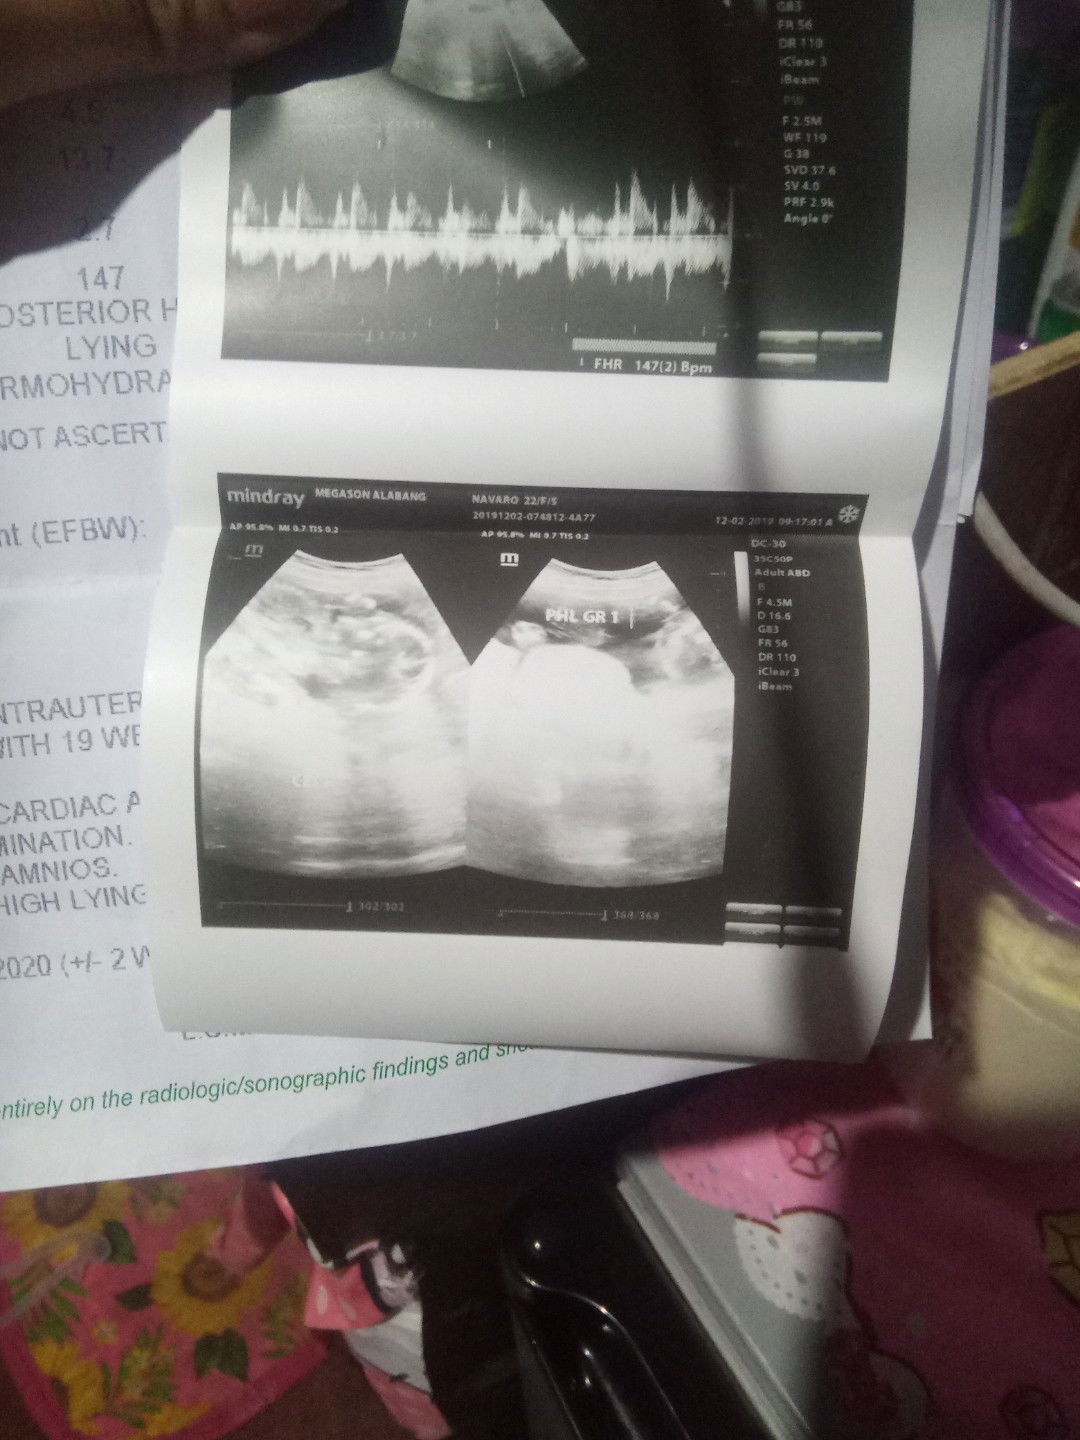

Ano po tingin niyo dtu its a girl po ba or a boy ? thankyou

Malabo masyado